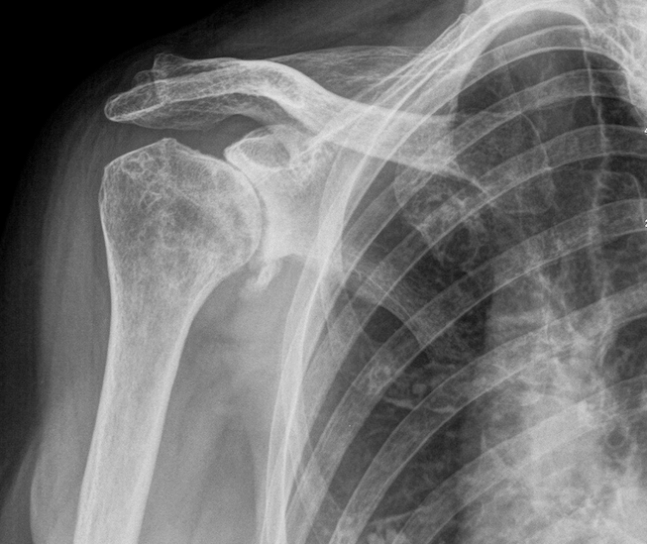

La protesi di spalla viene utilizzata in casi in cui l’articolazione gleno-omerale è compromessa a causa di :

- fratture della porzione prossimale dell’omero

- artrite reumatoide

- artrosi

- necrosi della testa omerale

- tumore